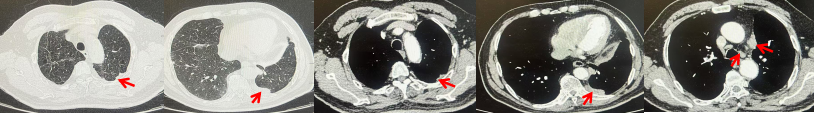

69岁男性,无糖尿病、高血压、心脏病等基础疾病,无吸烟、饮酒史,无肿瘤家族史。2023.06.07行胸部CT检查:右肺上叶胸膜下见肿物影,大小约33mm×22mm,边缘可见分叶,考虑恶性病变可能性大,双肺间质改变(如图1)。2023.06.14行“单孔胸腔镜下右肺上叶切除、肺门及纵隔淋巴结清扫、胸膜粘连松解术”;术后病理:(右肺上叶)腺癌(低分化,实体型占60%,不良腺体占40%),局灶伴神经内分泌标记表达(CD56、Syn),可见STAS及胸膜侵犯,未见确切神经侵犯及脉管内癌栓;(气管切缘)净;(淋巴结)未见转移癌0/26(2组0/2;4组0/6;7组0/2;对侧7组0/8;10组0/2;11组0/3;12组0/2;13组0/1)。术后分期pT2aN0M0 IB期,术后NGS基因检测:无驱动基因突变,PD-L1(22C3)TPS<1%。术后定期复查。

2024.11.19患者出现右侧胸痛,复查胸部CT检查示右侧胸膜肿物,大小约31mmX24mm,右侧4、5肋骨骨质破坏,考虑转移(如图2)。建议患者穿刺活检取病理明确诊断,患者拒绝,经MDT会诊后结合影像学表现及病史考虑为胸膜转移,肋骨转移,分期为rT0N0M1a IVA期,DFS仅仅17个月。2024.12.05起行信迪利单抗联合培美曲塞+卡铂方案治疗4周期,复查胸CT评效PR(如图3)。之后给予信迪利单抗+培美曲塞维持治疗6周期,期间复查CT评效PR(如图3)。目前信迪利单抗+培美曲塞维持治疗中,截止至目前PFS约为8个月,治疗期间未出现明显毒副反应。

图1:患者手术前(2023.06)胸部CT肺窗及纵隔窗

图2:患者胸膜及肋骨转移(2024.11)胸部CT肺窗、纵隔窗及骨窗

图3:患者免疫联合化疗治疗后胸部CT,(A、B)图展示信迪利单抗联合培美曲塞+卡铂治疗

4周期(2025.02)疗效,(C、D)图展示信迪利单抗+培美曲塞维持治疗6周期(2025.07)疗效